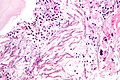

Pulmonary hamartoma

General

Microscopic

Features:

• No cytologic features of malignancy.

• Fat.